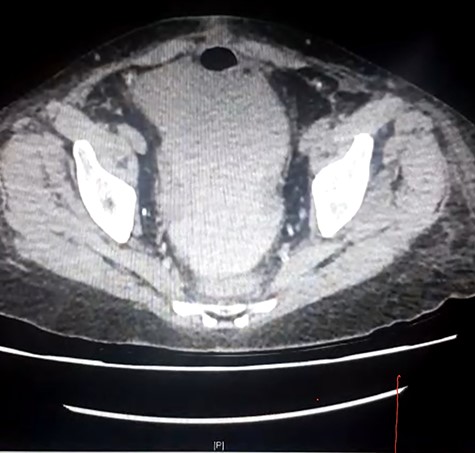

Repeat CT imaging with IV contrast at the referring hospital prior to transfer revealed large volume free fluid intraperitoneally with ongoing dilatation of the renal collecting system which was contrast filled. The distal ureter was not seen entering the bladder. The free fluid in the pelvis also demonstrated increased density raising concern for haematoma or possibly intravenous contrast (Figs 2 and 3).